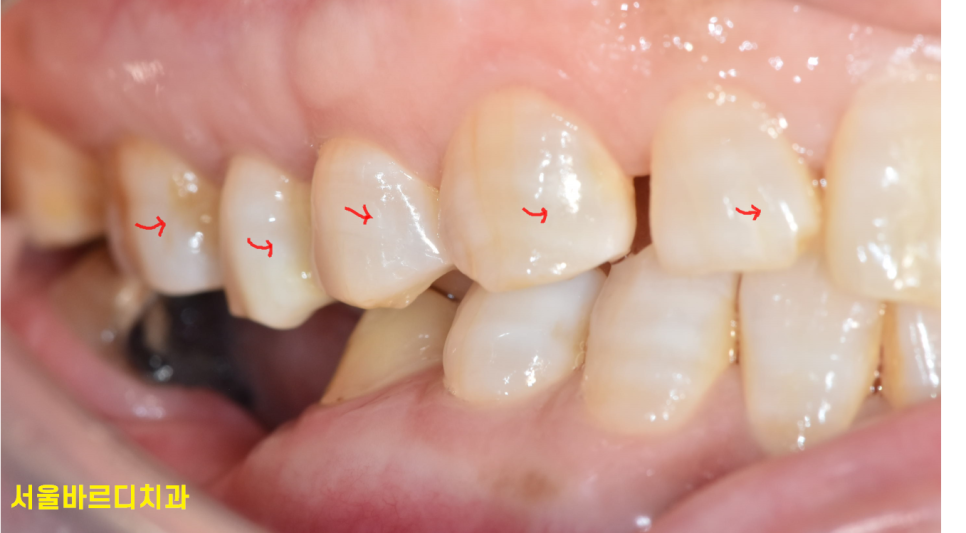

앞니의 비뚤어진 치아를 고르게 피거나

치아 사이 틈을 없에는 치료입니다.

오늘 환자분처럼 앞니 사이 틈이 있어서 보기 싫거나

약간의 삐뚤빼뚤함을 가지고 있을 때 진행합니다.

약간의 치아 사이 공간이 있는 경우

치아를 앞으로 조금씩 움직여 공간을 메꾸면 되기 때문에

치아 삭제없이 앞니 부분교정이 가능합니다.

치아에 손상도 없고